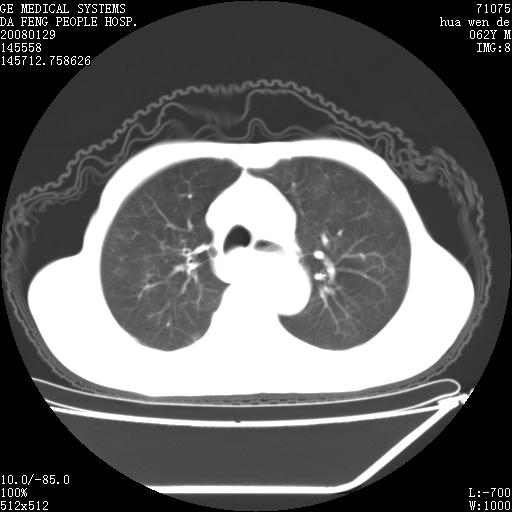

男性,67岁。作肺部检查时发现

理由:1、右上肺内病灶,空洞形成,有液平。

2、肺内多处炎症。

1.整个食管扩张,未见明显占位性病变,贲门区亦未见明显占位病变,考虑:贲门失驰缓症;

2.右上肺病变边缘可见毛刺,囊壁厚度不均匀,周围境界较清楚,未见炎性渗出性影,右上肺外带可见片状影,边缘不清,考虑:肺癌伴空洞形成、右上肺炎。

15楼主分析有道理,胸腔胃除外,那么考虑贲门失驰缓症并肺部化脓感染(吸入性)可能。

肺内病灶位于右肺中叶,食道扩张后导致咽部功能受影响,吸入气管可能是存在的。

食管全程扩张,壁均匀不厚,喷门失弛缓症

右上肺空洞可见液平,临近肺野磨玻璃密度,考虑1.结核2.脓肿